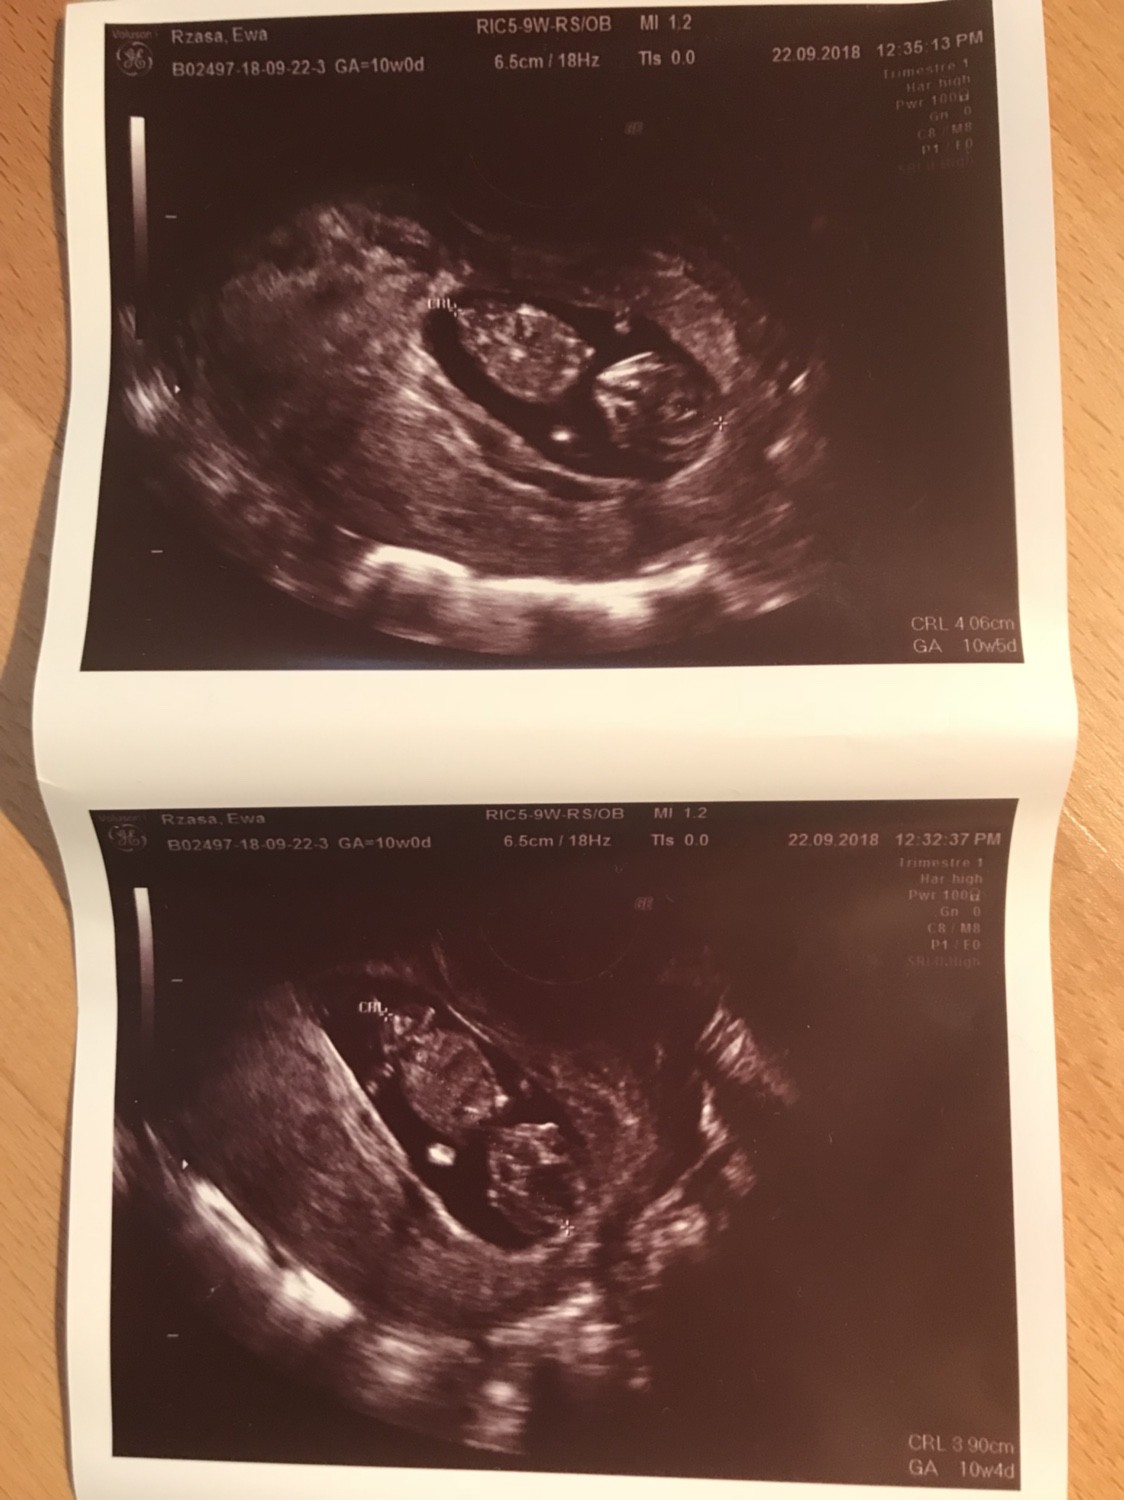

Ja tez mialam dzis wizyte, wracalam z londynu 4 godziny w korku, myslalam, ze uswierkne w samochodzie! Z maluszkiem jest wszystko w porzadku[emoji173]️, 4cm 10+4/5wiec praktycznie co do dnia zgadza sie z transferem, krwiaczek sie wchlonal i jest ok. Maluszek machal raczkami i jakies koziolki fikal, az trudno uwierzyc, ze tam w srodku taka impra sie odbywa ;) wiec jak narazie kamien z serca i czekam na prenatalne 3 pazdziernika. A tu fota kosmity i wracam dalej nadrabiac forum. :)

IMG_1151.JPG